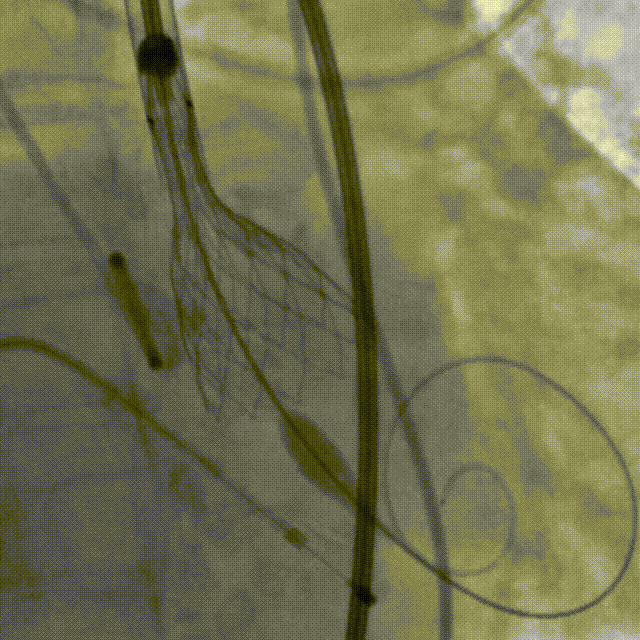

陶主任对人工瓣膜进行部分回收后再定位

术中,人工瓣膜部分释放时,由于受自体瓣膜的挤压导致人工瓣膜下滑,陶主任立即对人工瓣膜进行了回收再定位,到达预期位置后精准释放,手术结果令人满意。